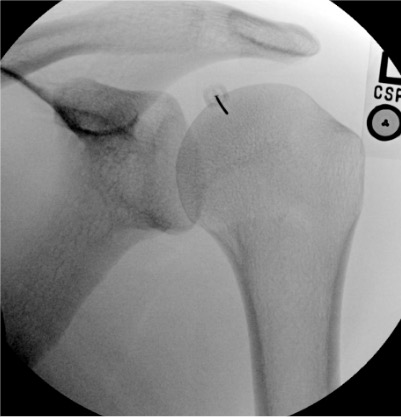

Shoulder

Finding

Fluoroscopic Appearance

Full-thickness rotator cuff tear

Contrast fills the subacromial/subdeltoid bursa = communication with glenohumeral joint through full-thickness tear

Biceps tendon sheath filling

Normal — the long head biceps tendon sheath communicates with the glenohumeral joint

Capsular adhesion (frozen shoulder)

Reduced joint volume; capsule does not distend; obliteration of axillary and subscapularis recesses

Bursal communication (shoulder): absent / present (subacromial = full-thickness RCT)

Shoulder: missing subacromial bursal fill

If evaluating for RCT by arthrogram, upright positioning after injection shows bursal fill better; take fluoroscopic images in multiple positions